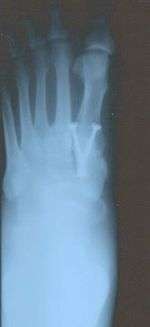

Syndesmosis procedure addresses specifically the two fundamental problems of metatarsus primus varus deformity that gives rise to the bunion deformity. They are leaning and instability of the first metatarsal bone . Syndesmosis procedure uprights the leaning first metatarsal bone with strong binding sutures between it and the second metatarsal bone (Fig. 2) and then also stabilizes it uniquely by creating a fibrous connecting bridge between these two bones (Fig. 3,4). First metatarsal bone can be readily realigned is because by definition of the metatarsus primus varus deformity its first metatarsal is abnormally loose and mobile.